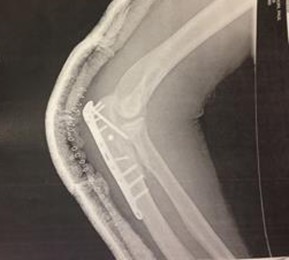

When Mark was operating his bicycle against traffic, one sunny afternoon, a motorist failed to see him, crossed over the white fog line and struck him. Mark was thrown from his bicycle and suffered devastating injuries including a fractured leg and a fractured arm and wrist which required surgery and hardware to put him back together.